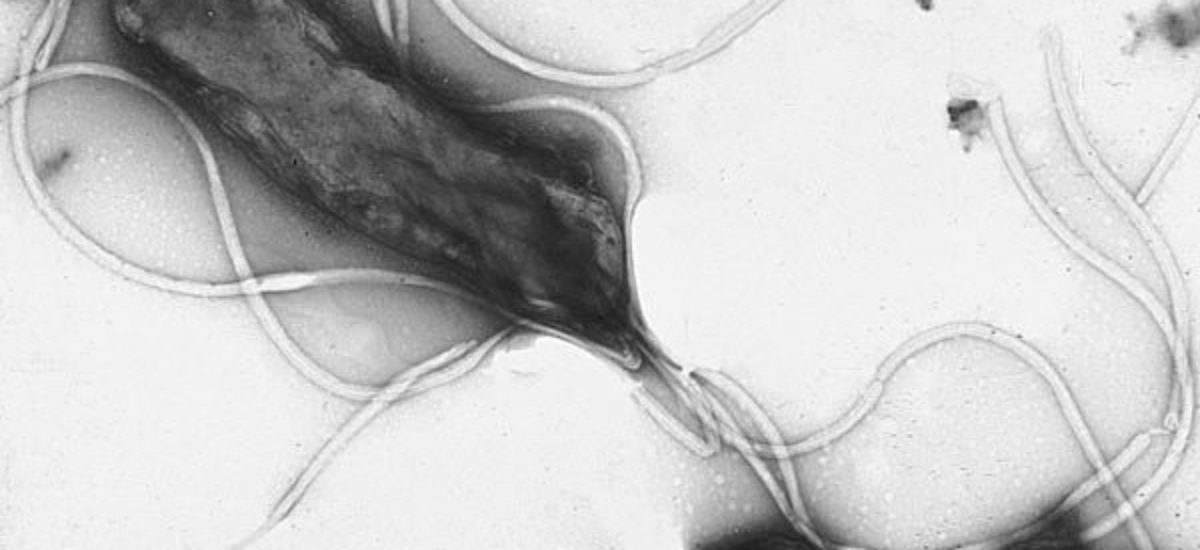

La Helicobacter pylori es la bacteria responsable de la mayoría de úlceras y de la gastritis crónica. Por sus características espirales, debilita la capa protectora e infecta el mucus del epitelio del estómago y la primera parte del intestino delgado (duodeno). Vive exclusivamente en el estómago humano y es el el único organismo conocido que puede sobrevivir en condiciones tan ácidas. Los datos epidemiológicos disponibles señalan que aproximadamente la mitad de la población mundial está infectada por H. pylori, que se suele contraer durante la edad infantil.

Una infección de larga duración en el revestimiento interno del estómago puede desembocar en una inflamación crónica que provoque lesiones precancerígenas